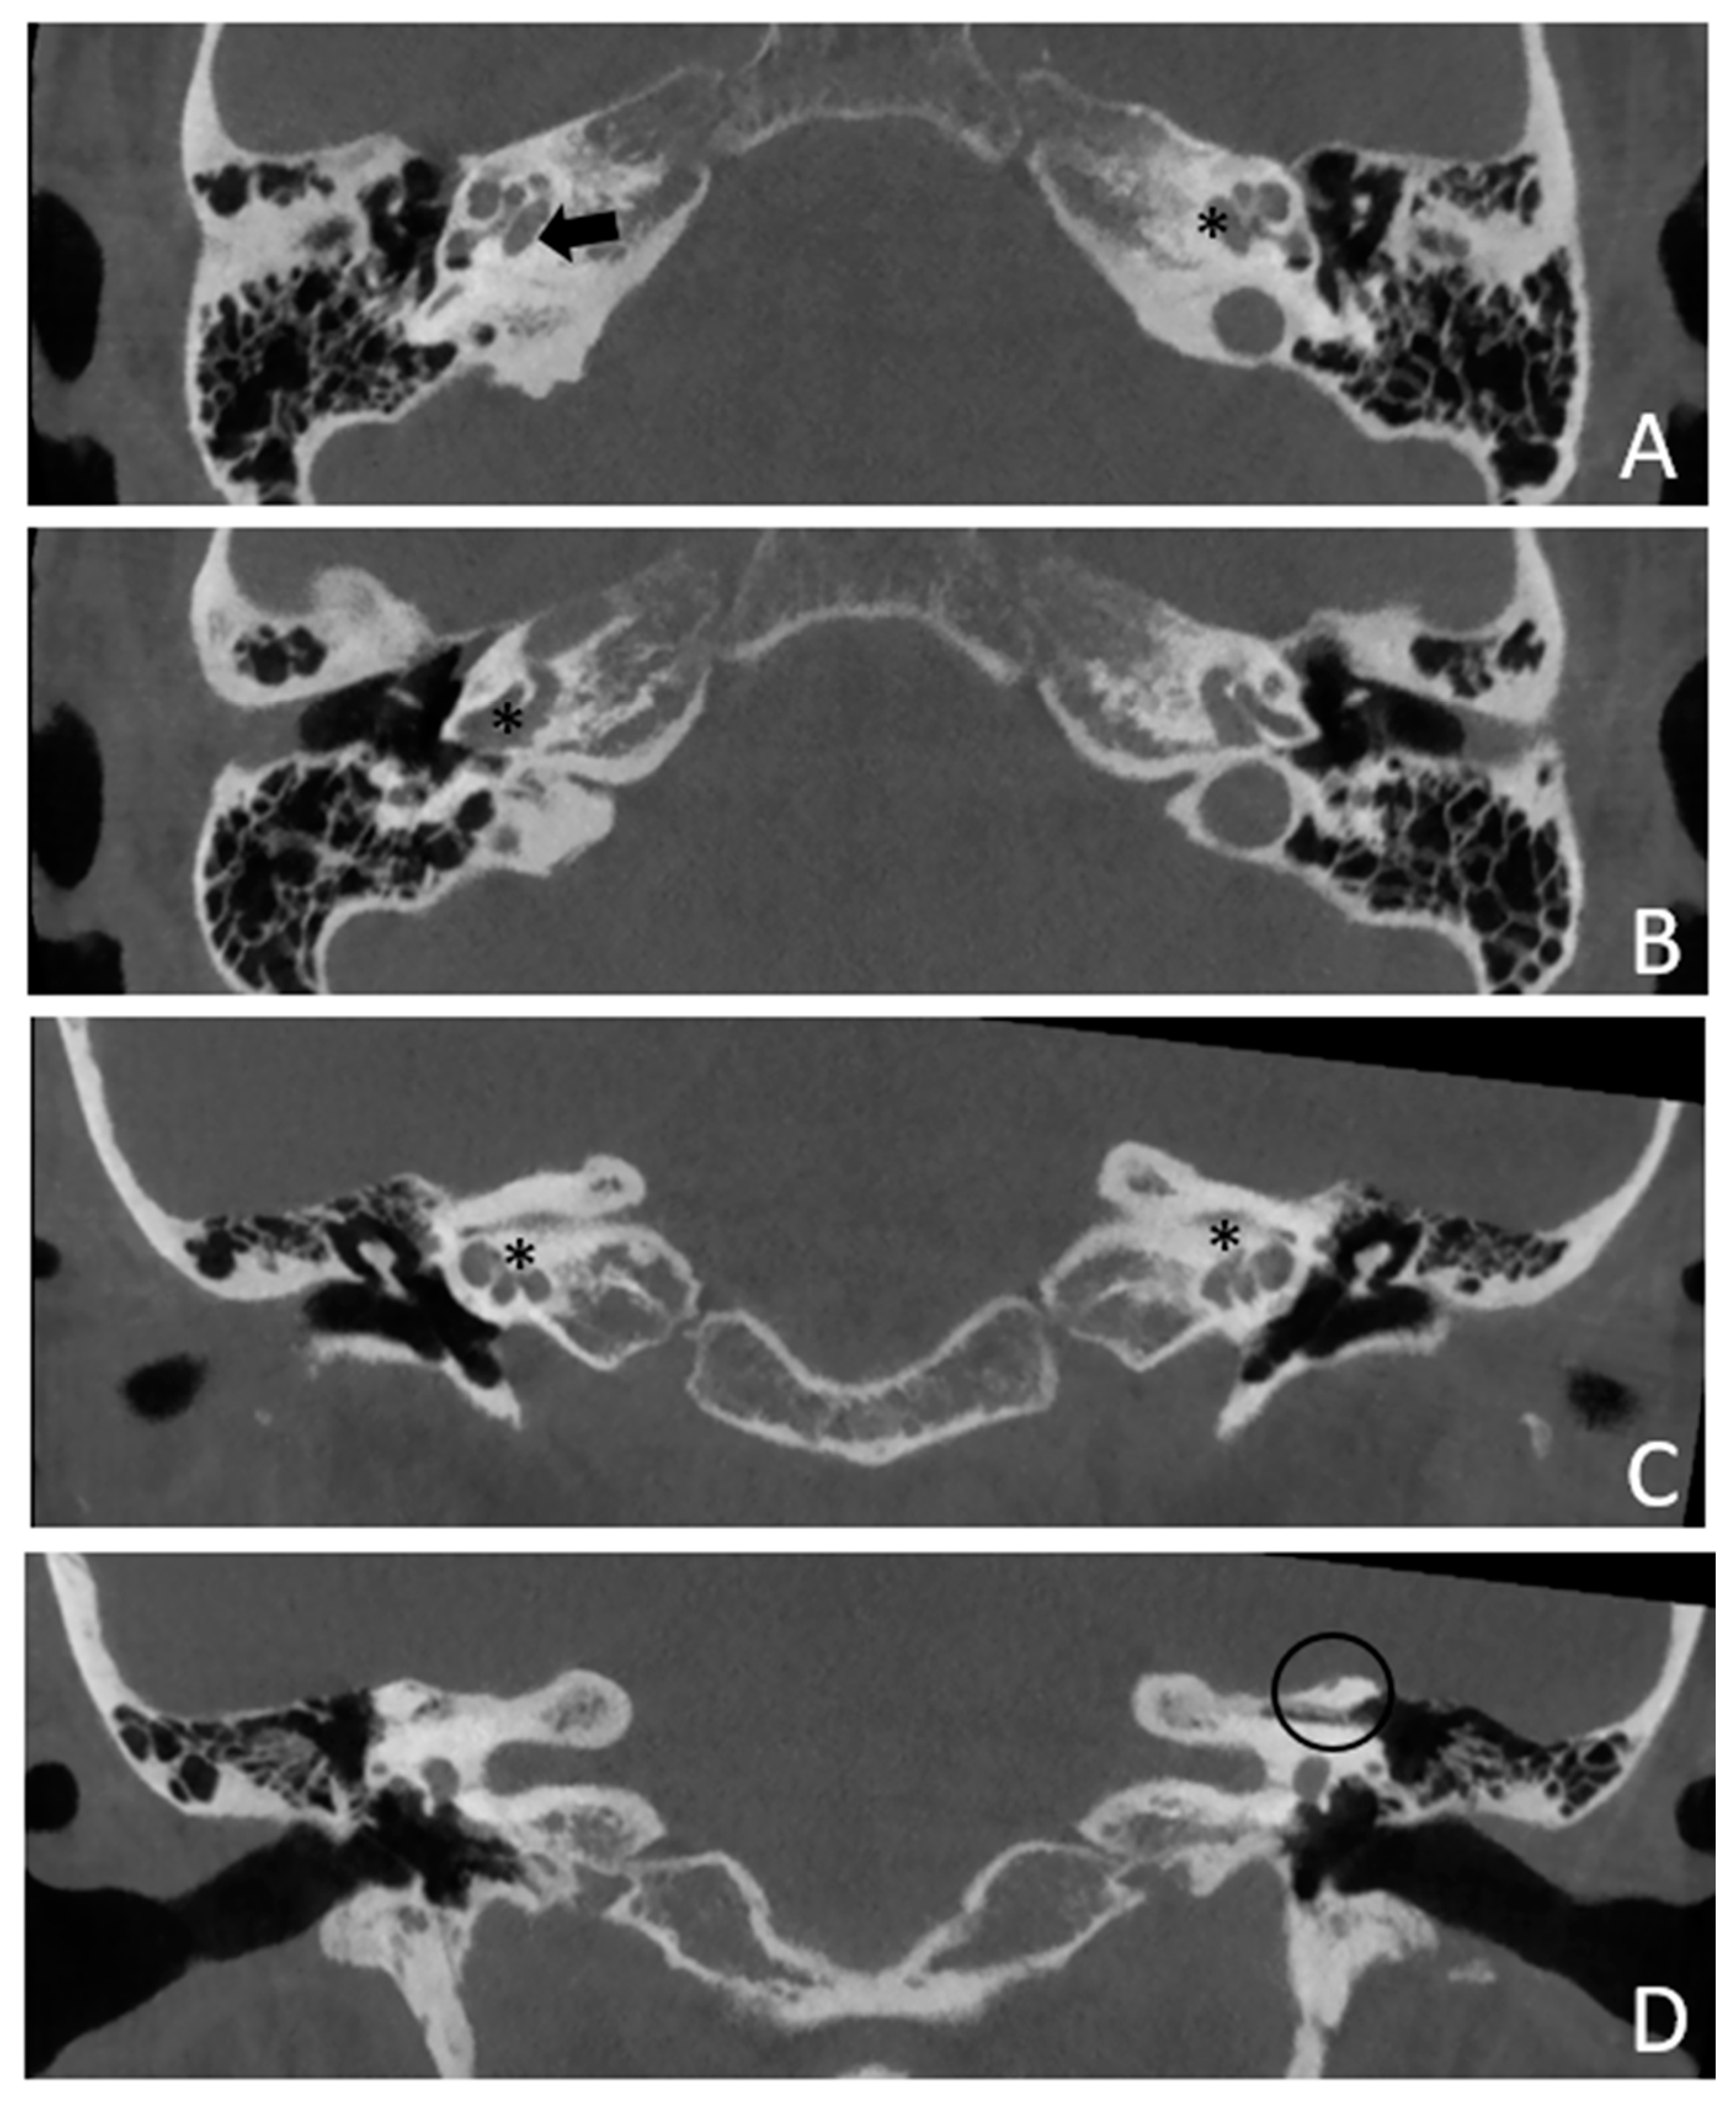

Figure 5. CT images of patient #3 with bilateral otosclerosis and SSCD of the left ear. A and B, axial plane; C and D, coronal plane. A cavitating osteorarefation around the cochlea is clearly visible. The communication of the cavity with the cochlea is indicated by asterisks. The arrow indicates the origin of the cavity from the IAC. The circle indicates the dehiscence of the SSC on the left side.